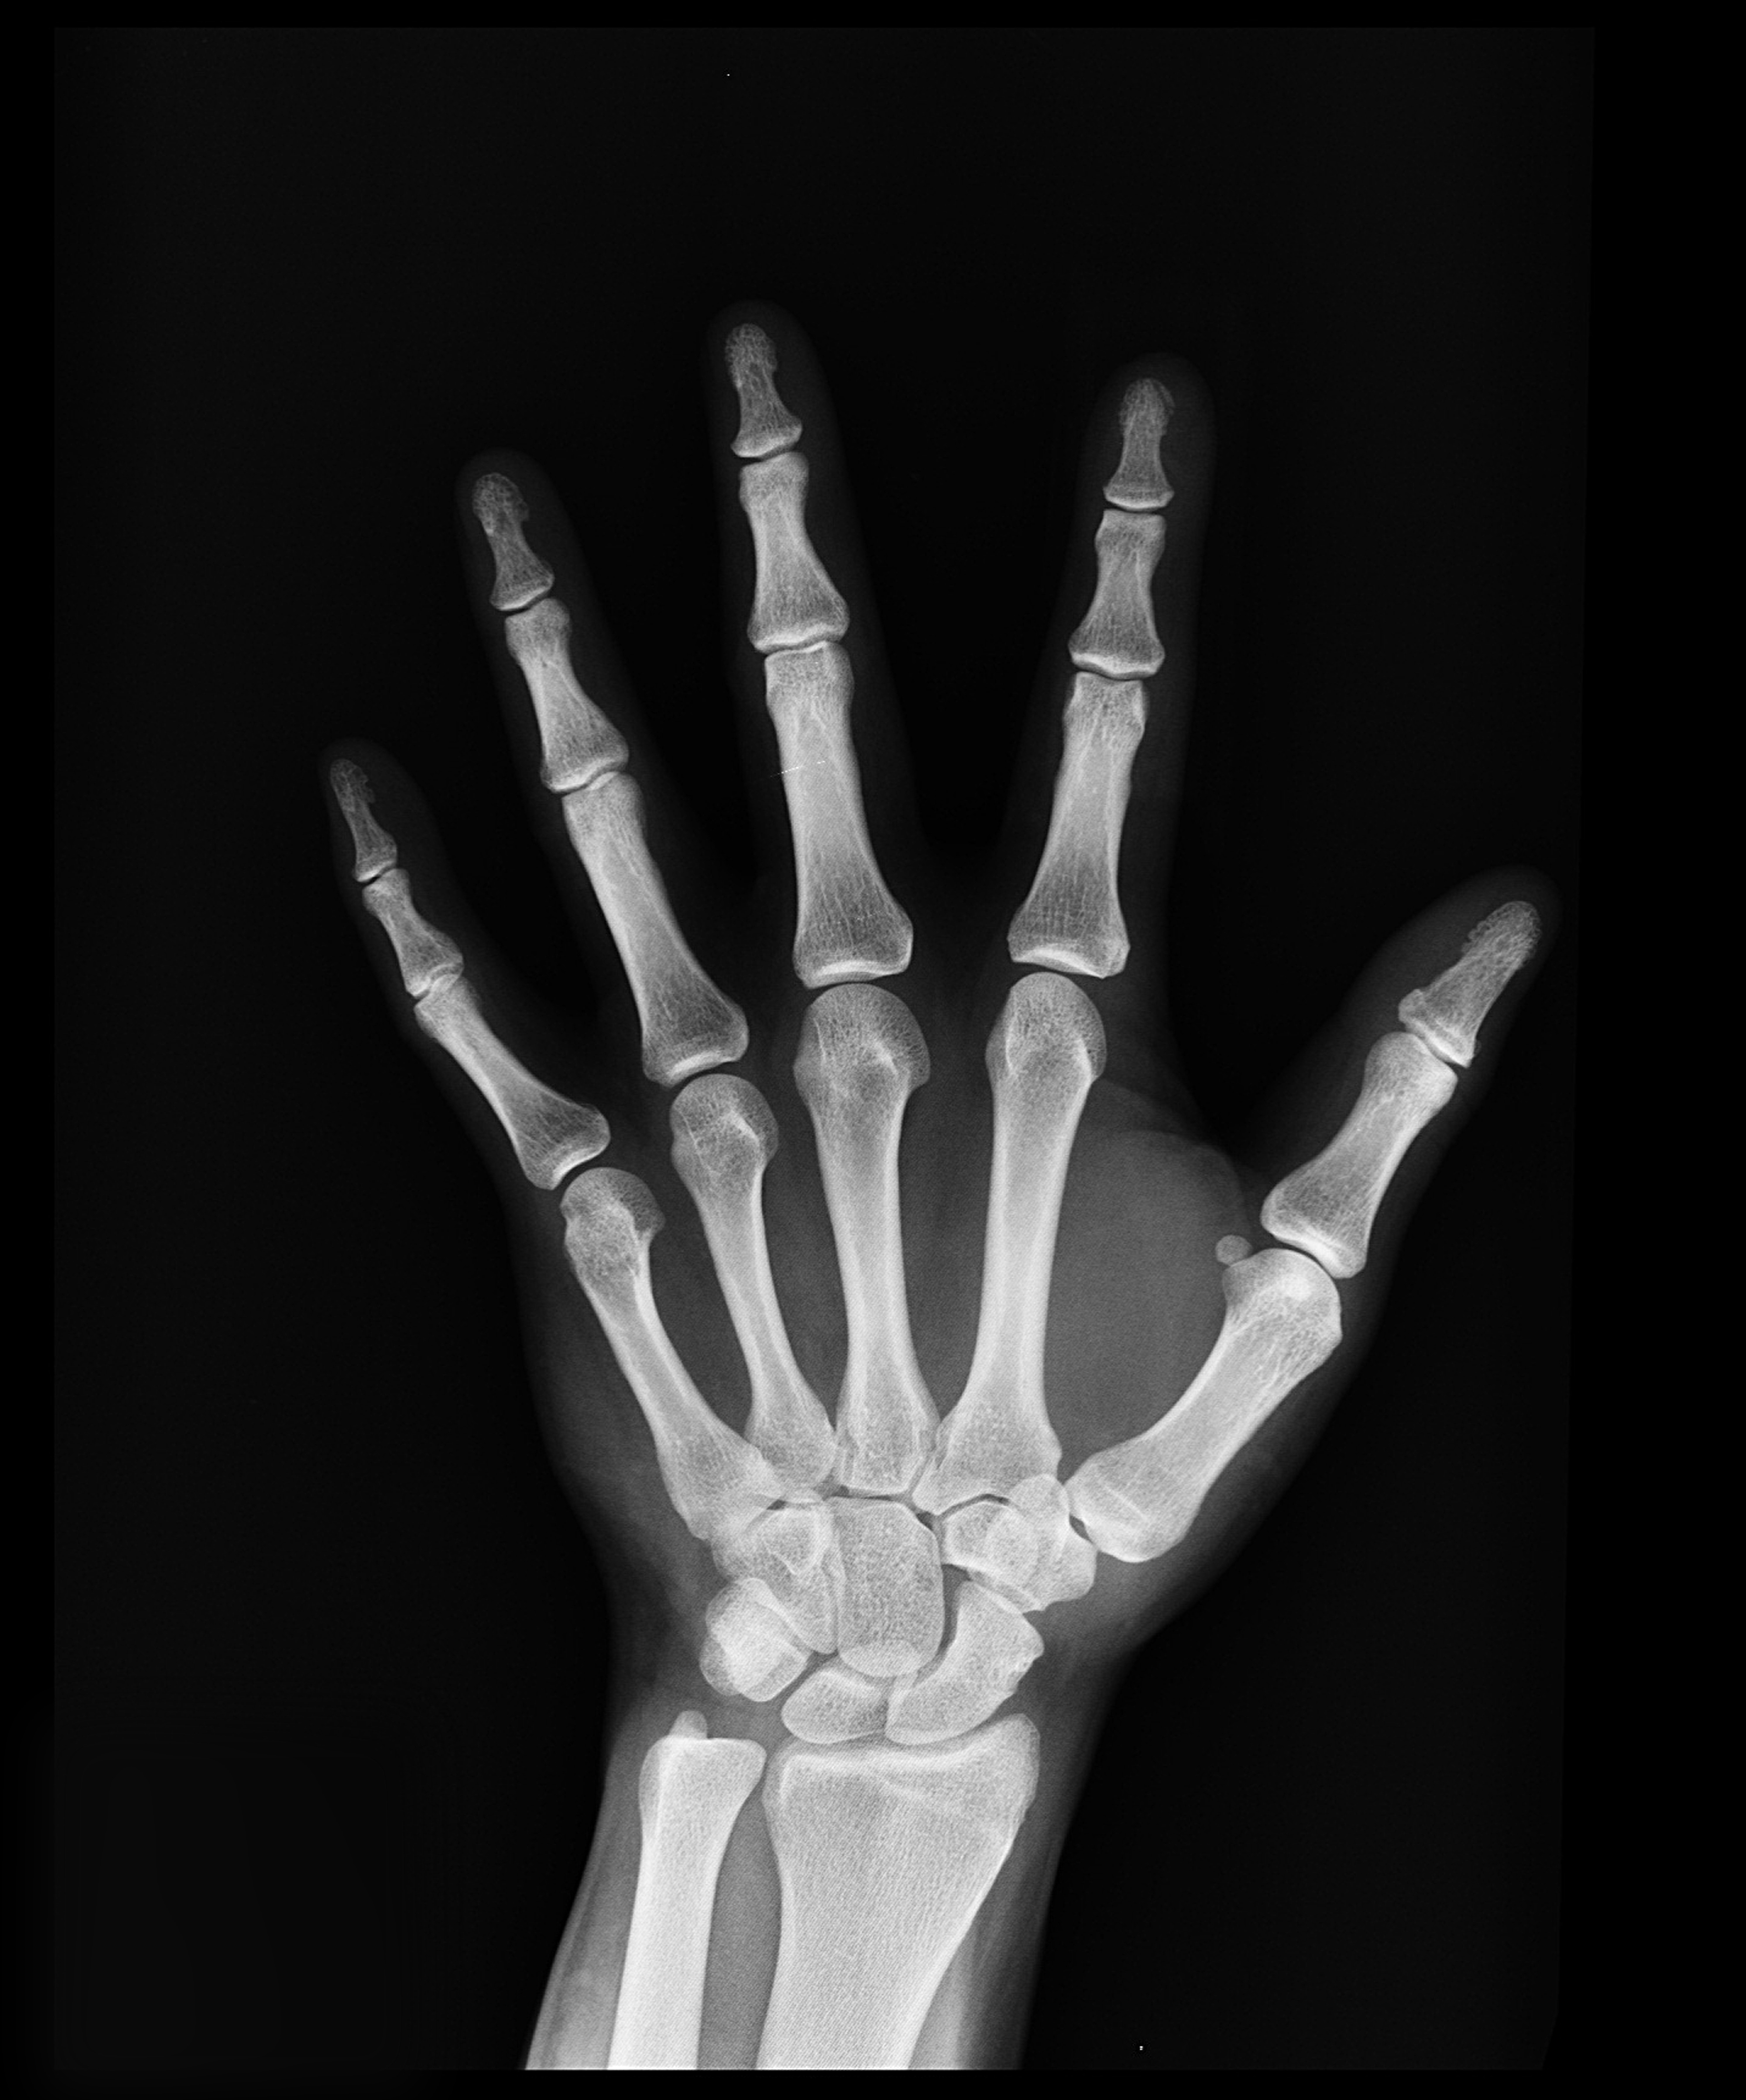

Brittle bone disease is a hereditary disorder that causes your bones to break easily, usually without any kind of trauma, such as a fall [1]. The condition is also known as osteogenesis imperfecta (OI), which means "imperfectly formed bone."

Brittle bone disease is inherited or passed down through families [2]. It's caused by a problem in a gene that's intended to produce a protein called collagen. Collagen is a protein found in the body that helps to form and strengthen bones. If you don't get enough of it, your bones weaken and break easily.

Brittle (weak) bones are common in people with osteogenesis imperfecta. The majority of people with the disease have broken bones at some point in their lives. A child with OI may have hundreds of shattered bones during birth in severe cases.